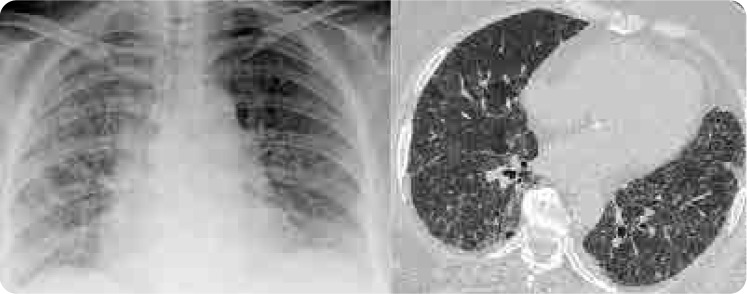

Case: A 65-year-old female patient with rheumatoid arthritis (RA) presented with shortness of breath and a non-productive cough after 15 years of stable MTX treatment. Chest X-ray revealed bilateral ill-defined infiltrates, and high-resolution computed tomography (HRCT) showed diffuse ground-glass opacities. All diagnostic tests for infection were negative. Suspecting MTX-associated HP, MTX was discontinued, leading to significant clinical improvement.